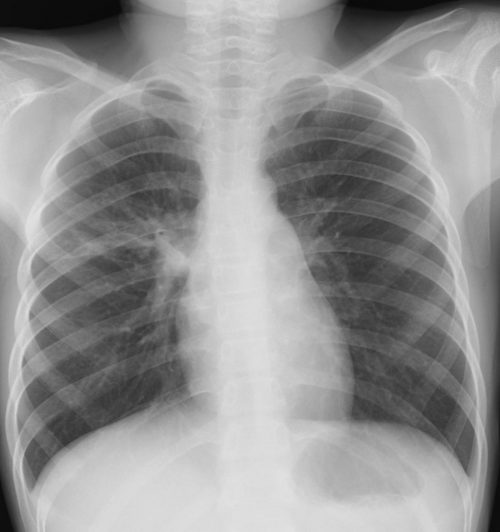

外来でよくみられる肺炎、マイコ・クラミジア・肺炎球菌・ウイルス(RSウイルス・hMPV・インフルエンザウイルスA・B)について実際に経験、外来で治癒した症例を提示します。軽症な変化のものが大多数ですが中には重症なものも紛れていて、注意が必要になります。

【マイコプラズマ肺炎】